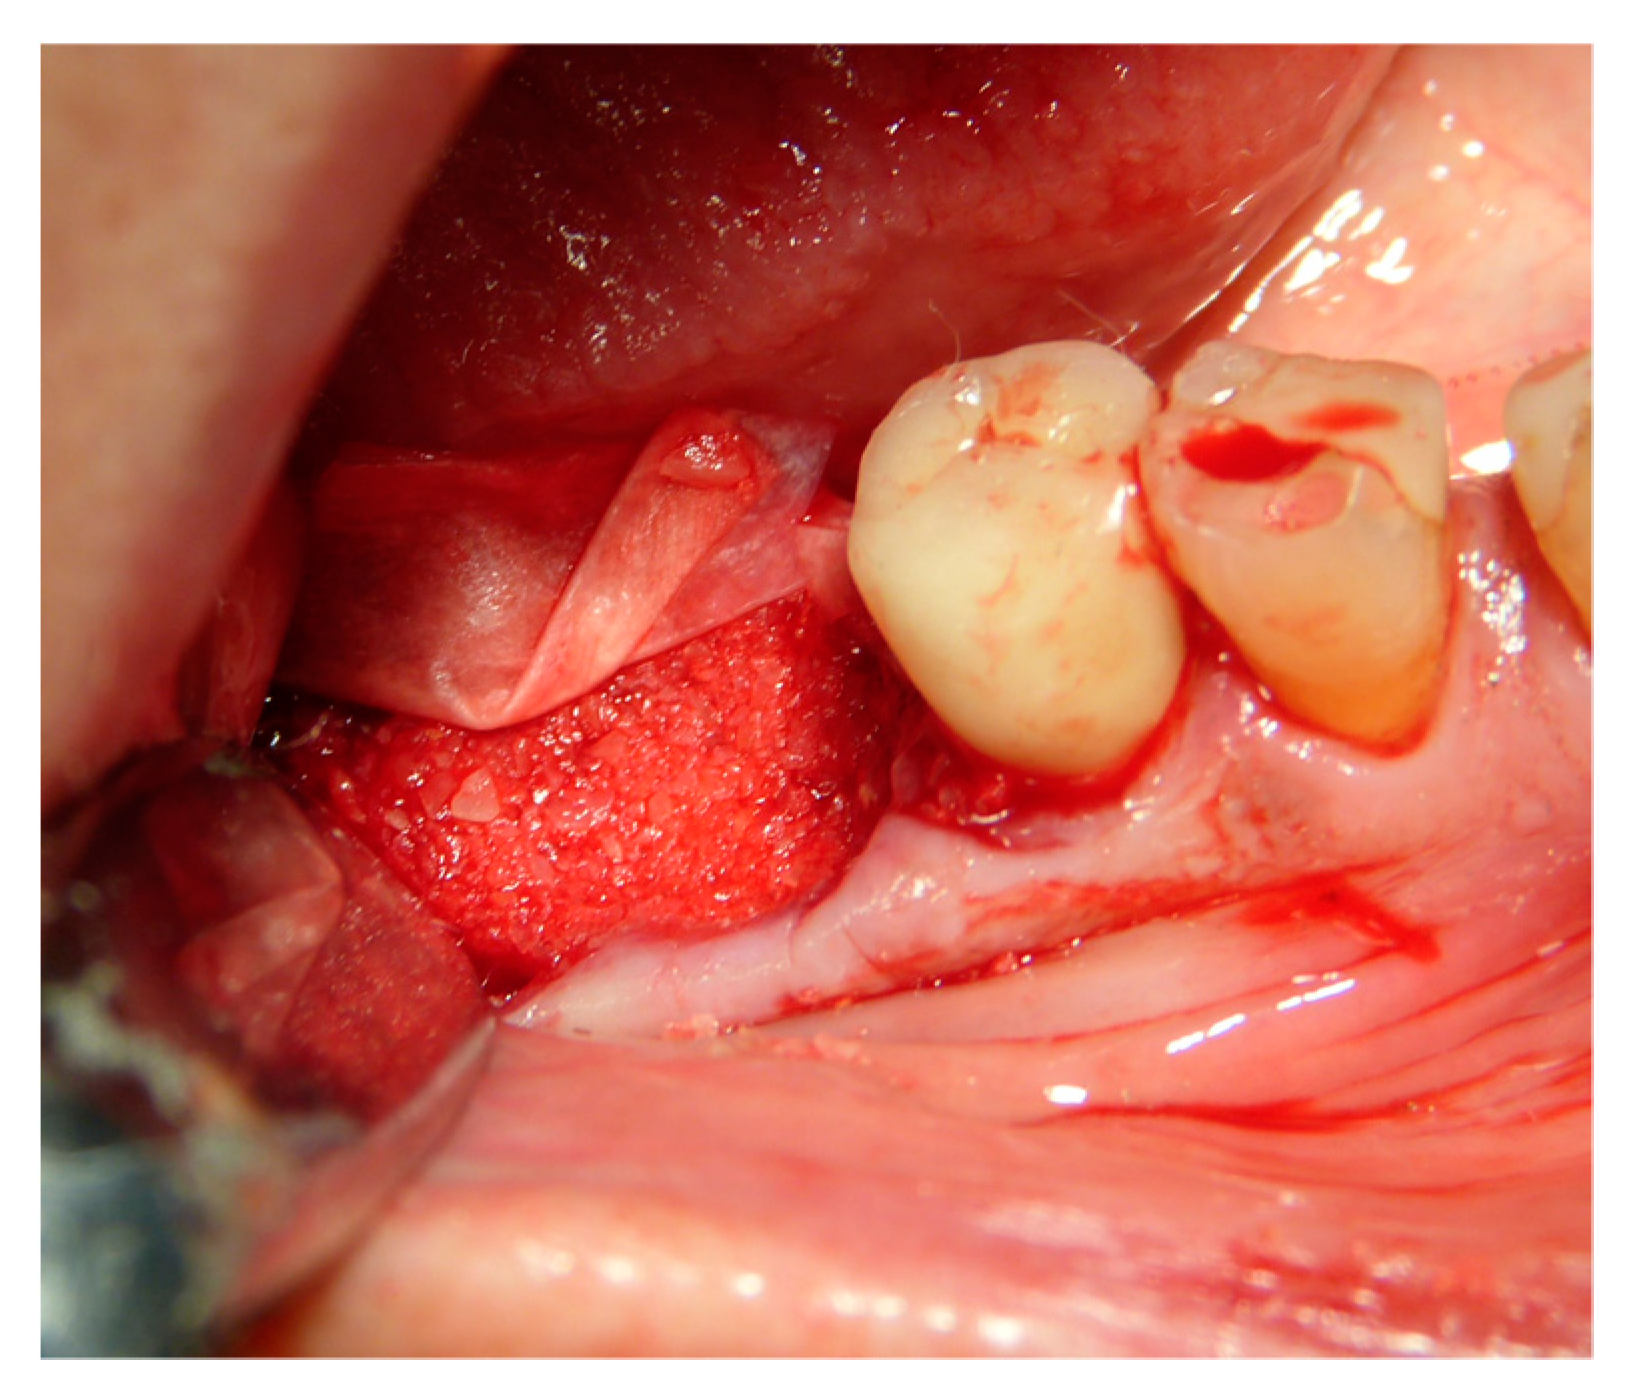

The vertical average defect was 9.16 mm, buccal lateral/palatal 7.0 mm, and mesio-distal 10.3 mm. The measurements were intraoperatively performed with a millimeter periodontal probe. The endodontic material mechanically cleaned before the tooth was placed inside the Tooth Transformer device. The endodontic material was removed using a drill bur with the attention to cut the canal in excess with the aim to remove all the cement. No surgical complications were registered. Pre and post-operative X-rays (section from CBCT) were collected from the same case (Figure 1, Figure 2, Figure 3 and Figure 4). After four months, 13 histological and histomorphometrical evaluations were performed (Figure 5). The Bone Volume/Total Volume average (BV%) was 41.47 (S.D. ± 11.51), the Residual Graft/Total Volume average (Graft%) was 16.60 (S.D. ± 7.09), and the Vital Bone/Total Bone average (VB%) was 21.89 (S.D. ± 9.72). No extraneous material (gutta-percha or cement) was detected in all samples (Table 3).

The faraway graft procedure follow up is 40 months and the near graft procedure follow up is 9 months (Average 24.5 months). The faraway implant follow up is 35 months and the near implant follow up is five months. The success rate of the tooth graft procedure is 99.1% (one site was infected and lost the regeneration and the implant) (Figure 6, Figure 7 and Figure 8). In all cases, after the all implants were inserted, complete osseointegration after proper healing period was achieved. After the healing period, hard and soft tissues were stable (Figure 9, Figure 10 and Figure 11). The healing of soft tissues after grafting procedures was particularly free of complications. The implant success rate was 98.94% (one implant failed).

Figure 9. Reopening after three months.